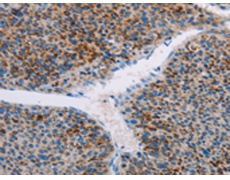

ELISA, IHC |

IHC positive control: |

Human liver cancer |

IHC Recommend dilution: |

25-100 |